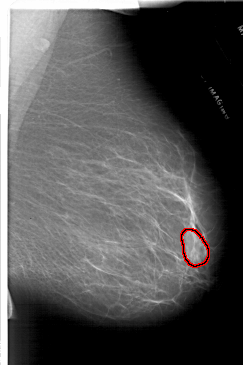

FILE: A_1717_1.RIGHT_CC.OVERLAY

TOTAL_ABNORMALITIES 1

ABNORMALITY 1

LESION_TYPE MASS SHAPE LOBULATED MARGINS ILL_DEFINED

ASSESSMENT 4

SUBTLETY 3

PATHOLOGY BENIGN

TOTAL_OUTLINES 1

BOUNDARY

RIGHT_CC LINES 6601 PIXELS_PER_LINE 4261 BITS_PER_PIXEL 12 RESOLUTION 43.5 OVERLAY